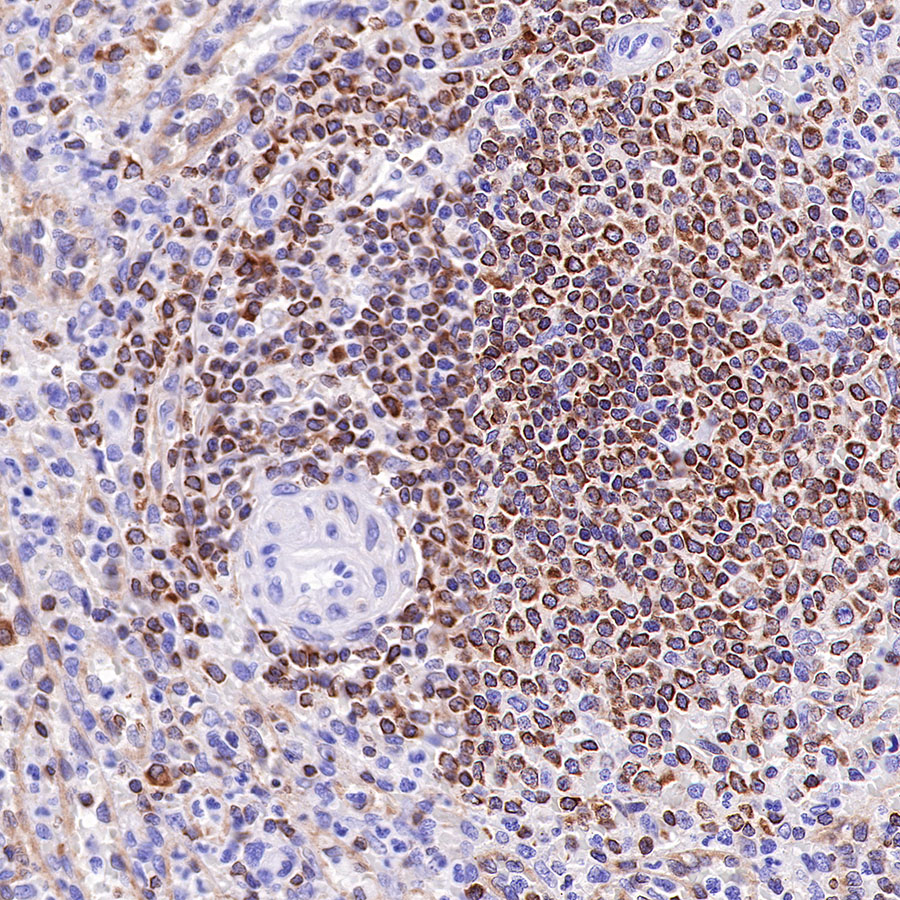

Picture

Immunohistochemistry